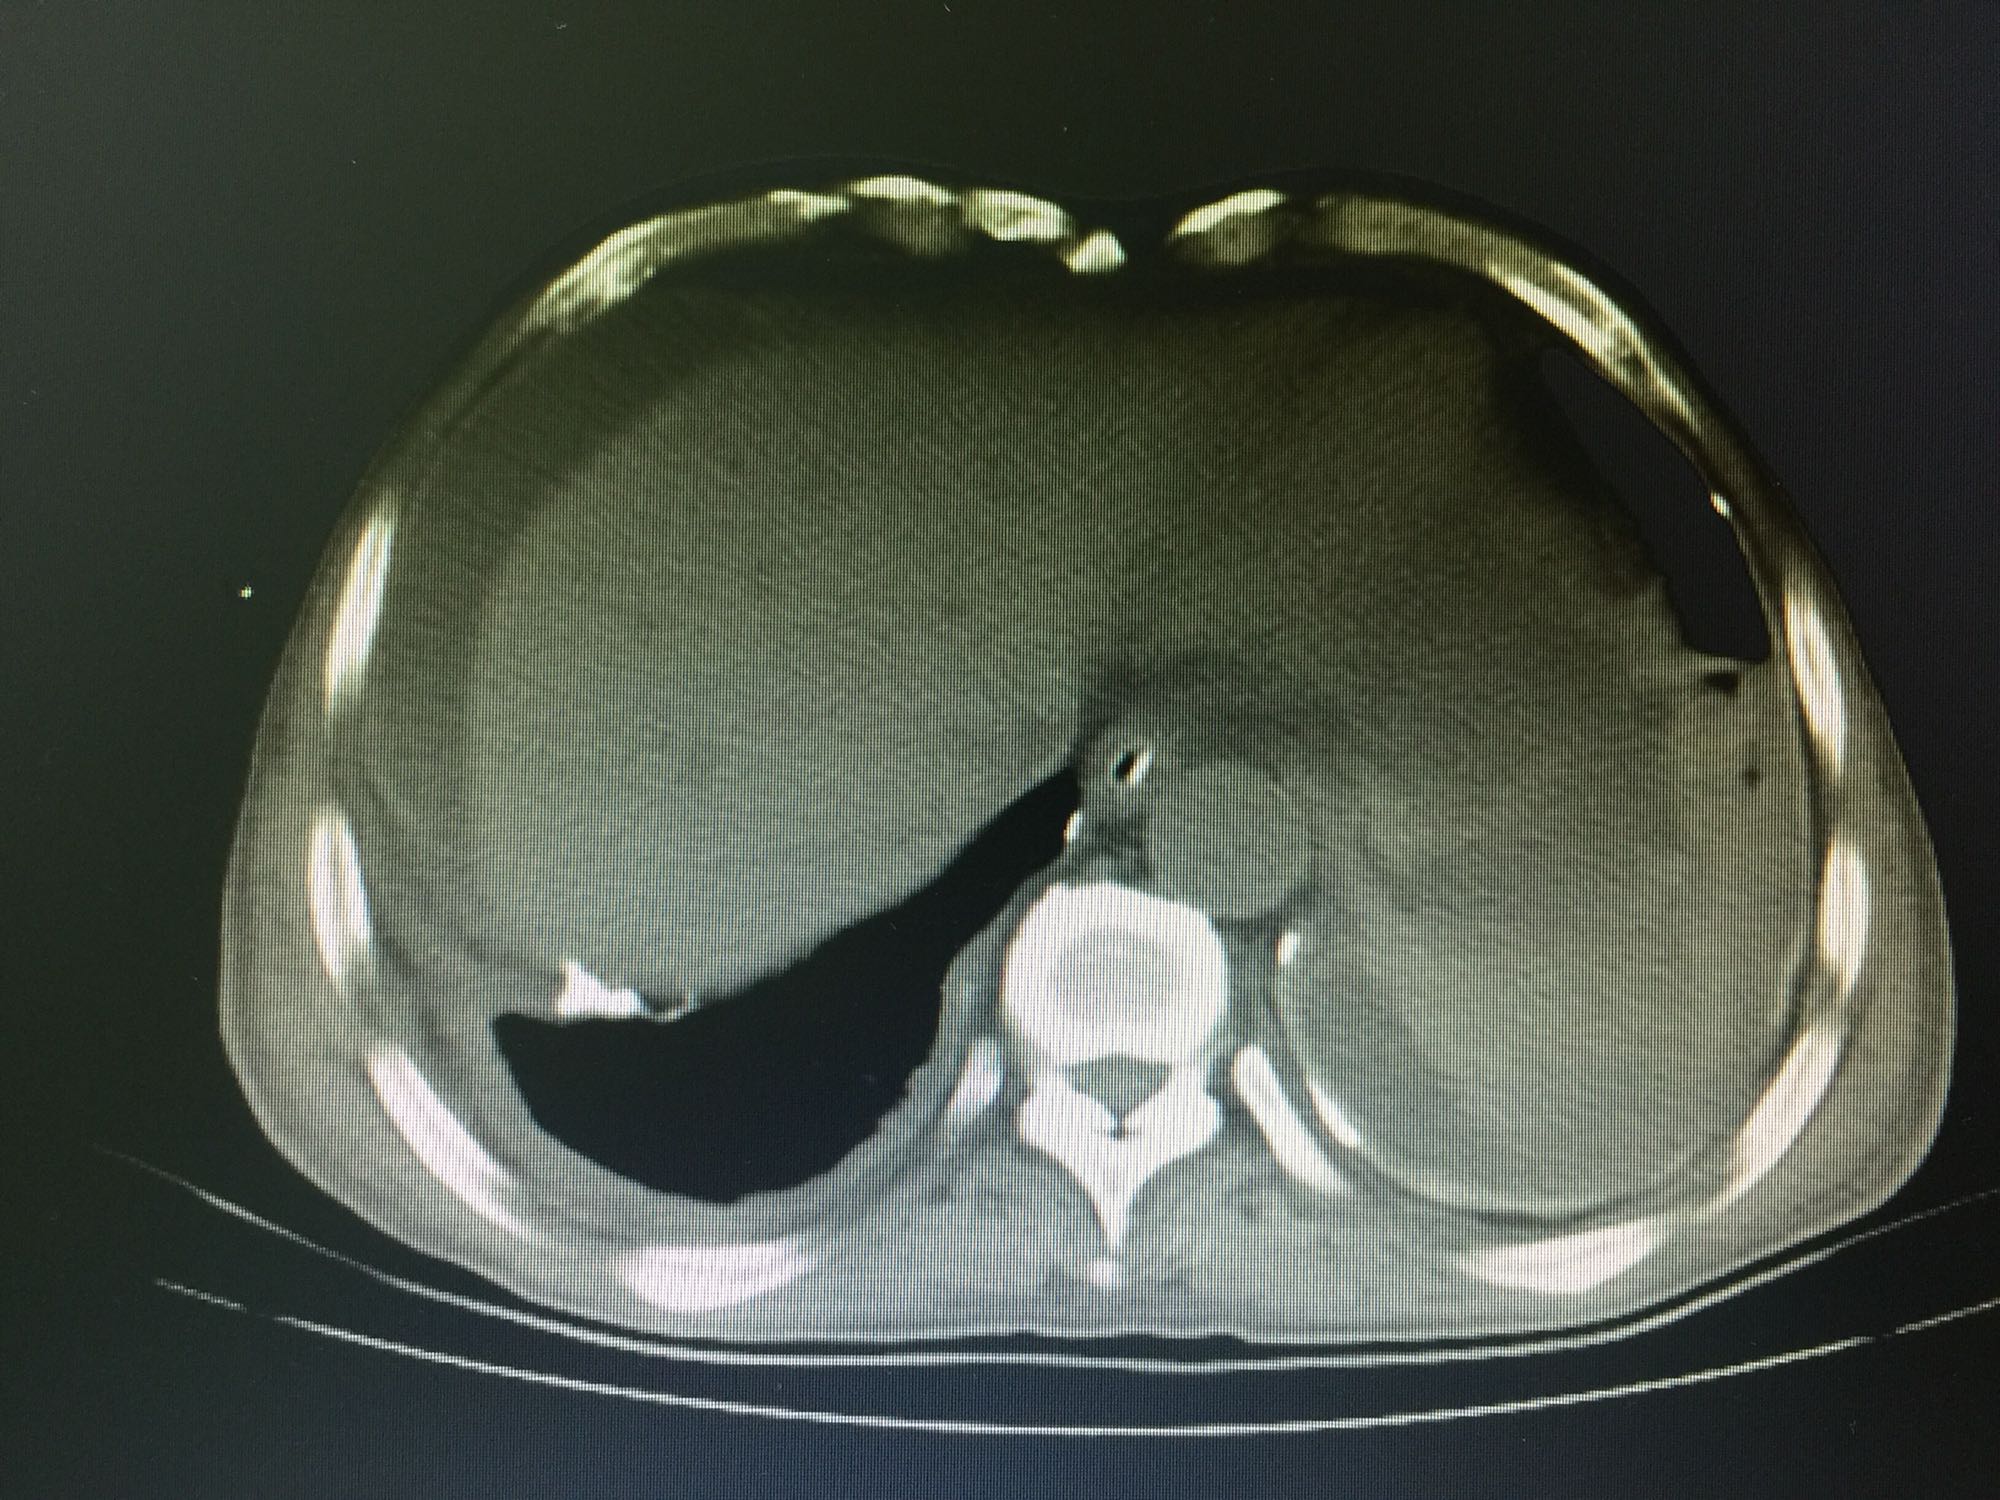

诊断:直肠癌,结肠息肉。 治疗:直肠低位前切除术,术后7天盆腔引流量逐渐增多,伴腹痛、发热,血像明显增高,腹部CT见腹腔大量积液,吻合口处结构不清晰,直肠旁间隙见条索状增强影;再次手术证实为吻合口漏。